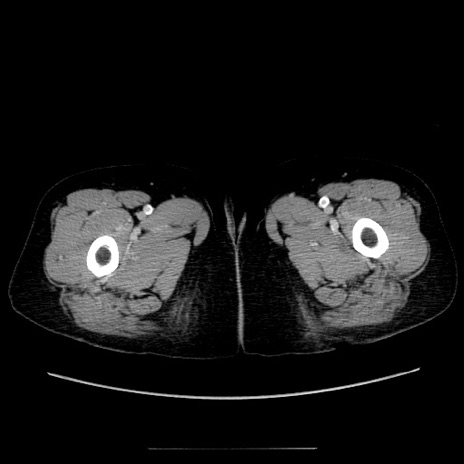

症例5(横断像)

【症例】70歳代女性

【主訴】お腹が張る

【現病歴】1週間くらい前から腹部膨満の自覚あり。昨日夜から増悪したため、本日救急外来受診。

【身体所見】意識清明、BT 36.5℃、BP 165/106mmHg、HR 80bpm、SpO2 98%、腹部:膨満、軟、自発痛・圧痛なし、触診にて不快感あり、腸蠕動音:減弱

【データ】WBC 12600、CRP 1.04